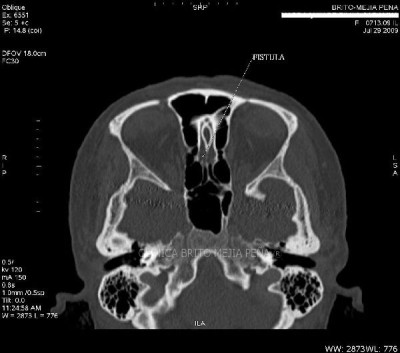

Fístula LCR axilar